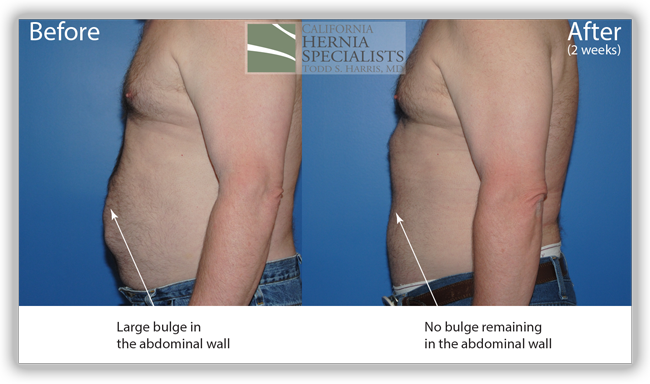

In the images below we compare the pre-operative photos to the post-operative photos taken just 2 weeks after his surgery.

The patient continued to lose weight after his surgery. He was followed for 6 months and did very well throughout this time returning to normal activities after about 4-6 weeks.

This technique requires more surgical time, recovery time, and usually several days in the hospital. However, this patient chose to proceed with the open hernia repair. Below are some of the pictures from his surgery as well as post operative CT scan image and photos of the patient.

The patient is doing great months after his surgery with no bulge, no pains, and the ability to return to normal activities. He’s lost close to 40 pounds since he can now exercise again and is feeling back to normal.